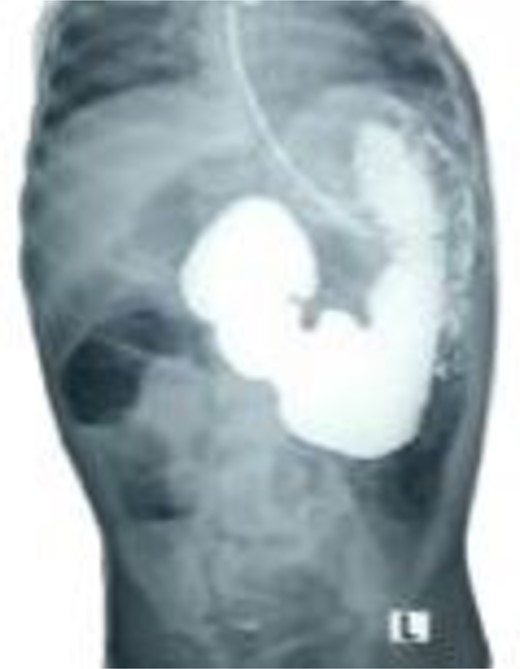

A 21-month-old girl presented with a history of bilious emesis since birth. The mother reported that the infant had several occasions of bilious emesis to a local doctor where she was managed as a case of dehydration. At 14 months of age, she was referred to a tertiary hospital for failure to thrive, where she was diagnosed with malrotation and underwent a Ladd’s procedure. However, the bilious vomiting continued. Upon arrival at our hospital, she was severely emaciated, dehydrated, and pale. Abdominal examination revealed visible epigastric peristalsis and right upper transverse surgical scar. After rehydration and correction of electrolyte imbalances, an upper gastrointestinal series showed signs of partial duodenal obstruction (Fig. 1). Abdominal exploration through the previous incision was done with findings of multiple adhesions that were gently released. The cecum was found in the left iliac fossa, and the appendix was not found. Potential causes of CDO such as malrotation, annular pancreas, and intestinal duplication were ruled out, following the duodenum, a PDPV was found causing the obstruction (Fig. 2). A diamond-shaped duodenoduodenostomy was performed, leaving the PDPV tunneled behind the anastomosis. The patient had a smooth post-operative recovery, gaining 1.7 kg in three weeks. Six months later, she was thriving, with her weight in the 90th percentile for her age.

Selected cut of an upper gastrointestinal contrast study showing dilated and elongated stomach, dilated first and second part of the duodenum, delayed passage of the contrast, and scanty gas in the distal abdomen keeping with features of chronic partial duodenal obstruction.